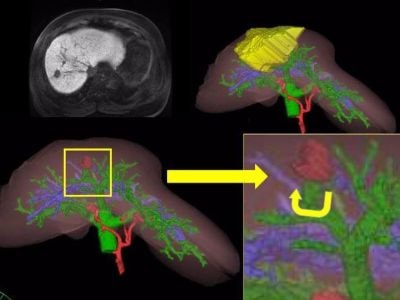

2016年4月から、多くの腹腔鏡下肝切除術は保険適応となっています。腹腔鏡手術の良い点は、お腹のキズが小さいため、手術後の回復が早いところです。しかし、従来のお腹を大きく開く手術にくらべて、手術の難易度が高いため、認定施設でのみ手術が認められています。当院では、日本内視鏡外科学会の技術認定医(肝臓)が中心となって、最新の画像処理技術を用い(シミュレーション・ナビゲーション)、腹腔鏡での手術を行っています。